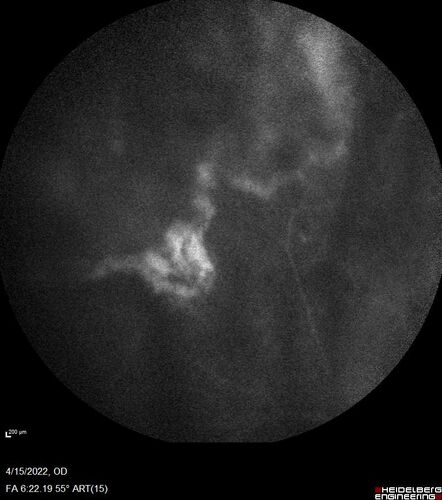

Toxoplasmosis right eye with diffuse retinal vascular whitening PCR confirmed

66 year old man The patient was doing fine until about 2-3 months ago.  He woke up with shadows and spots in the right eye.  Every blue moon he gets some pain in the right eye.  He has been getting treated with eye drops in the right eye.  Since this happened the vision is mostly the same.  Sometimes he sees better than other times.  He has not been treated with oral medications.

Negative labs: ACE, Lysozyme, RPR, HLA B27, Quant TB Gold, ESR (slight elevation of CRP)

PCR anterior chamber: negative herpes virus (HSV, VZV, CMV)

Positive for toxoplasmosis